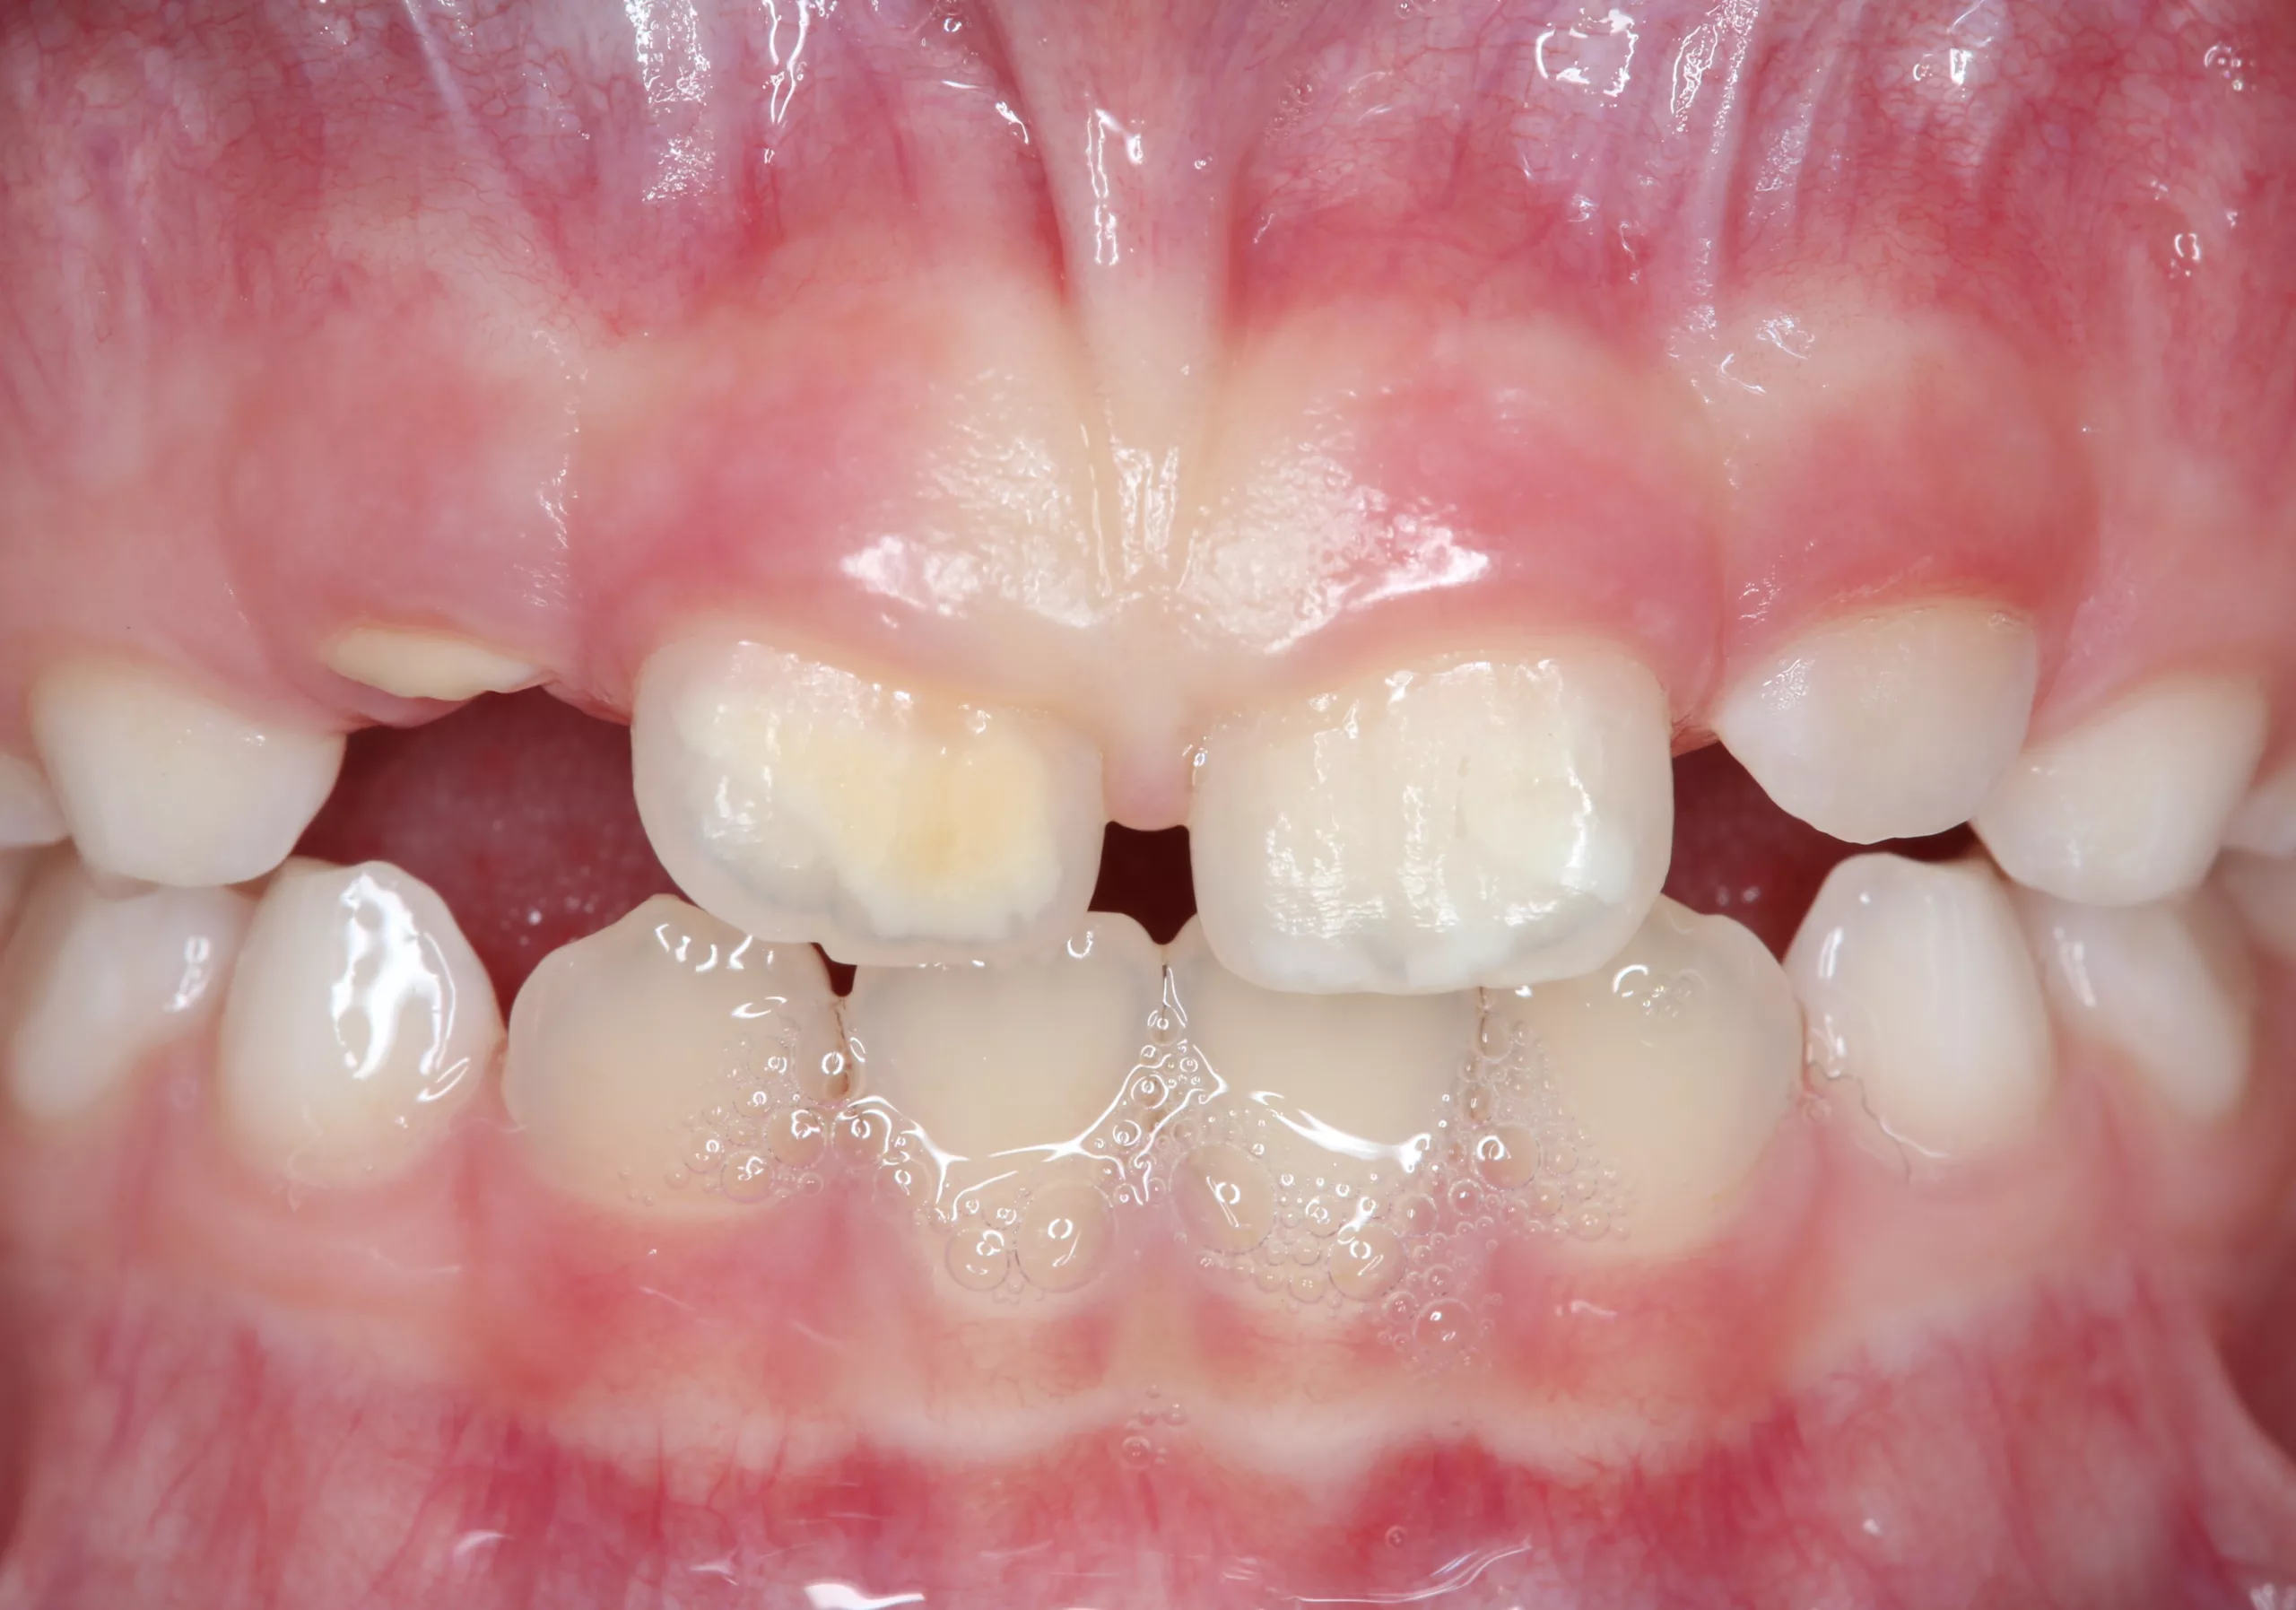

Der Begriff der „Molaren-Inzisiven-Hypomineralisation“ wird seit dem Kongress der European Academy of Paediatric Dentistry (EAPD) [1] im Jahre 2001 verwendet. Dieser beschreibt eine systemisch bedingte Hypomineralisation von ein bis vier bleibenden ersten Molaren mit oder ohne Beteiligung der Inzisiven [2] (Abb. 1 u. 2).

Klinisch imponieren die betroffenen Zähne durch abgegrenzte, weiß-cremige bis gelb-braune Verfärbungen bis hin zu prä- und posteruptiv entstandenen Schmelzdefekten mit zum Teil ausgeprägten Porositäten [2, 3]. Die Molaren sind dabei häufiger und ausgeprägter befallen als die Schneidezähne. Zu ergänzen ist, dass das klassische Bild des Befalls der Molaren und Inzisiven in der Zwischenzeit korrigiert wurde, da vereinzelt als MIH beschriebene Defekte mittlerweile auch an anderen Zähnen der bleibenden Dentition (7er, 5er, 3er) beobachtet worden sind. Des Weiteren finden sich vermehrt auch Hypomineralisationen an den zweiten Milchmolaren und den Milcheckzähnen [4, 5].

Für die Diagnose der MIH ist der klinische Befund entscheidend. Anamnestische Angaben sind dabei aufgrund der immer noch unklaren Ätiologie nur bedingt hilfreich. Aktuelle klinische Kriterien zur Erfassung der hypomineralisierten Zähne liegen von der EAPD vor [18], die wie folgt festgelegt sind: klar umschriebene Opazitäten, posteruptive Schmelzabbrüche, atypische Restaurationen und Extraktionen sowie atypische Hypersensibilitäten. Differenzialdiagnostisch müssen durch den behandelnden Zahnarzt u. a. folgende Krankheitsbilder in Betracht gezogen werden: erbliche Strukturanomalien (Amelogenesis imperfecta), postnatale Entwicklungsstörungen (Dentalfluorose, Schmelzfehlbildungen durch Tetrazyklingabe) und exogen bedingte Strukturanomalien (Trauma, apikale Entzündungen der Milchzähne [Turner-Zahn], Karies).